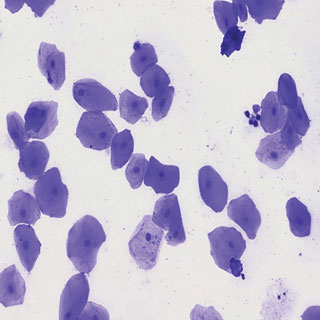

입안상피세포영구표본/입안표피세포영구표본/사람입안세포영구표본